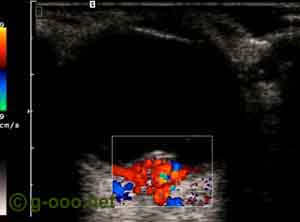

Hemangioma da coroideia do polo posterior do olho esquerdo, de uma mulher.

Aspecto da ecografia Doppler (power Doppler), que revela intensa circulação interna.